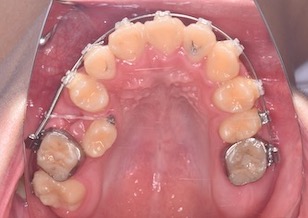

BeforeⅣは、右上顎第1小臼歯が萌出開始し、マルチブラケット装置を装着して牽引中のお写真です。

AfterⅡは、マルチブラケット装置を装着して右上顎第2大臼歯以外の上顎歯列が整直しているお写真です。